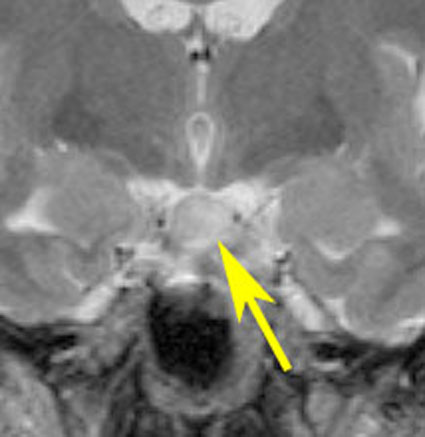

思春期早発で発症した幼児の視床下部過誤腫

視神経交叉の後方,乳頭体の前からぶら下がるようにしてあります

典型的な有茎状タイプです